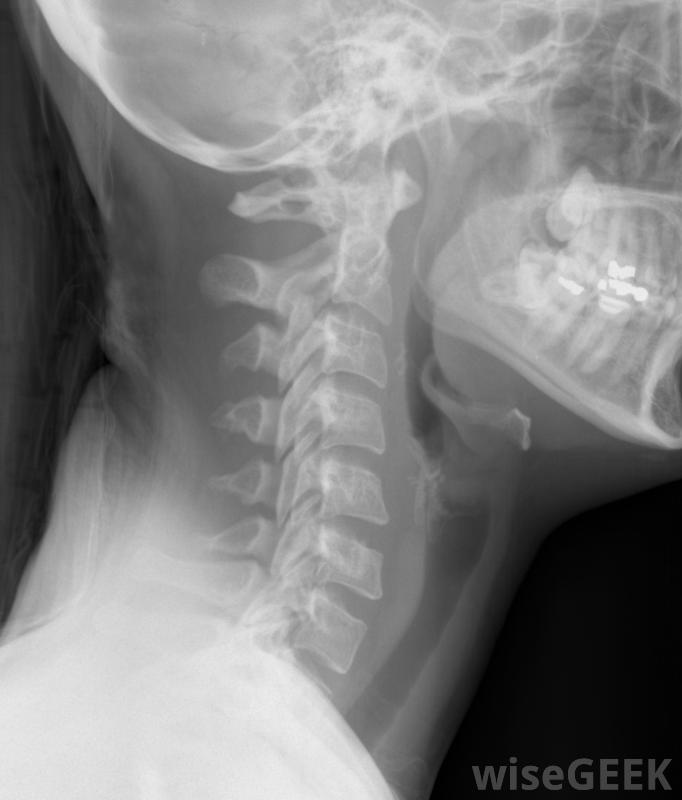

什么是彌漫性頸部隆起(Diffuse Cervical Bulge)?

脊柱由33個椎骨組成,其中7個構成頸椎。椎間盤位于每一個椎骨之間,起緩沖作用,幫助吸收沖擊。椎間盤由兩層組成。外層是一種纖維化材料,稱為環,內層是由較軟的材料制成,被稱為細胞核。頸部彌漫性膨出發生在環狀撕裂,并且細胞核的軟質物質從椎間盤的大部分突出或突出。頸部的X光片,包括頸椎。并不是所有的頸部彌漫性隆起都會出現癥狀。但是,由于頸部隆起會壓迫脊椎的神經,可能會出現各種癥狀。癥狀可能包括頸部疼痛,這種疼痛會輻射到肩部,手臂和手。人的手也可能有刺痛感或麻木感。在某些情況下,頸部和肩關節的放射狀突起可能是由于遺傳原因造成的頸部突出和頸部突出腰椎間盤突出。跌倒、車禍或重物搬運對頸部區域造成的損傷可能會導致一些人的頸部出現彌漫性活動對于椎間盤突出,有時建議行椎間盤切除術;t自行痊愈。醫生在體檢后做出診斷。醫生會記錄病史和運動范圍。通常會對脊椎進行核磁共振檢查,以確定脊柱的位置彌漫性頸部隆起。治療將取決于癥狀的嚴重程度。可以進行MRI掃描以確定彌漫性頸部隆起的位置如果癥狀較輕,非處方消炎藥可能會有幫助,或者可以開類固醇。對于疼痛更嚴重的患者,硬膜外注射或類固醇注射可以減輕疼痛。其他治療方法包括:,熱療和冰療法。冰可以減輕炎癥,熱敷可以放松肌肉。建議進行物理療法以提高柔韌性和伸展頸部。硬膜外注射可幫助患有嚴重疼痛的患者彌漫性頸部隆起對于沒有其他侵入性較小的方法幫助的人,手術可能是一種手段。一種被稱為椎間盤切除術的程序可以被執行。這包括移除突出或壓迫神經的椎間盤部分。在某些人中,重物會導致頸部隆起可能不可能在所有情況下都能預防頸部彌漫性隆起,但是有一些方法可以降低風險。使用適當的舉舉舉技術,例如彎曲膝蓋,不要拉緊頸部肌肉可能會有幫助。保持健康的體重和定期的鍛煉,可以加強整個脊椎,包括頸椎,可以保持椎間盤的健康。避免吸煙,因為吸煙會削弱椎間盤。吸煙會削弱脊柱間盤,增加人患彌漫性頸膨出的風險。